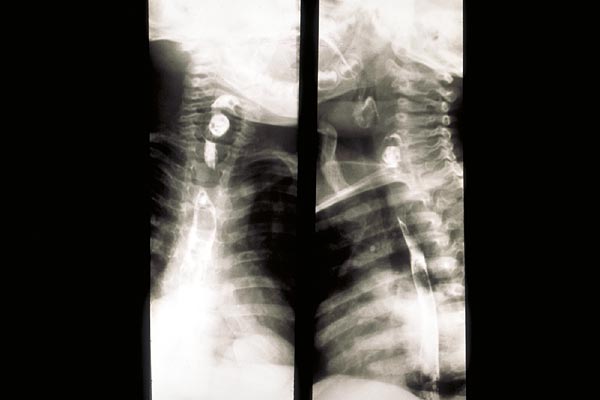

radiologischer Nachweis

|